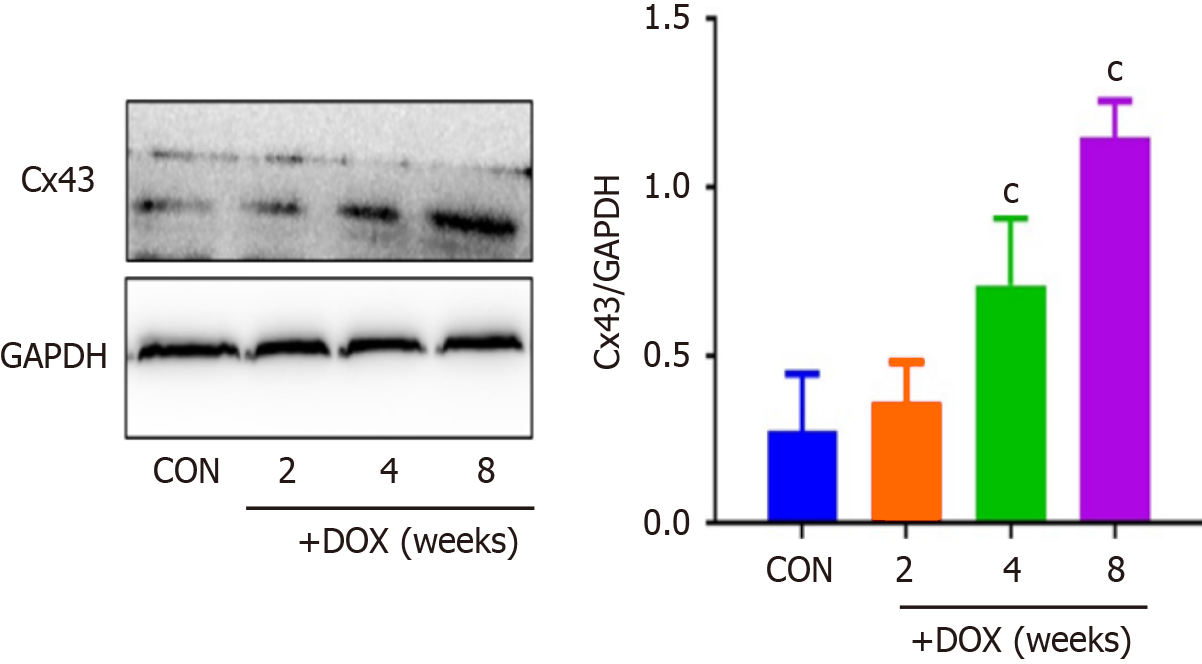

Western blotting revealed that the levels of Cx43 protein were significantly elevated in the DOX group compared with the CON group (Figure 4).

Calcium plays a necessary role in nerve impulse transmission, cell signaling, and maintaining calcium homeostasis in mammals. In our research, we discovered that DOX prolonged ventricular conduction time and conduction dispersion, and slowed heart rate. In addition, statistical analyses revealed that DOX prolonged the QT interval. The key structure for rapid electrical conduction between cardiomyocytes is the gap junction, a transmembrane channel for electrical and chemical coupling between cardiomyocytes, which is essential for maintaining cardiac rhythm, of which Cx-forming hemichannels are a major component. Cardiomyocytes express Cx40, Cx43 and Cx45, with Cx43 being the most widely distributed in the mammalian cardiovascular and nervous systems, and the main Cx expressed by ventricular myocytes. The mechanism by which DOX leads to the reduction of Cx43 protein involves several aspects, including oxidative stress, abnormal phosphorylation regulation, and activation of protein degradation pathways. DOX undergoes redox cycling in cells through its quinone structure, generating large amounts of ROS[29]. Excess ROS directly damage cardiomyocytes, and may also lead to structural and functional impairment of Cx43 by oxidizing key amino acid residues (e.g., cysteine and methionine) of the Cx43 protein[29]. DOX inhibits the activity of protein kinase (PK) A and PKC, which normally stabilize Cx43 by phosphorylating specific serine residues (e.g., Ser368 and Ser365) to stabilize Cx43 and promote its localization to the cell membrane[30]. In contrast, DOX may activate protein phosphatases (e.g., PP1 and PP2A), leading to dephosphorylation of Cx43, which in turn promotes its degradation via the ubiquitin–proteasome pathway[31]. It has been shown that DOX can upregulate the expression of E3 ubiquitin ligases (e.g. Nedd4 and ITCH) that recognize and ubiquitinate Cx43, thereby promoting its degradation by the proteasome[32]. DOX may also induce autophagic degra

It has been reported[22] that CALU plays an important role in the occurrence and development of acute myocardial ischemia, arrhythmia and other diseases. Our results also showed that expression of CALU was significantly decreased in the DOX group compared with the CON group. This indicated that expression of CALU was decreased by DOX. We found that DOX decreased rat body weight, and increased the heart weight–body weight ratio. DOX reduced expression of CALU due to Ca2+ overload, and increased apoptosis of myocardial cells. In vivo experiments showed that DOX reduced expression of CALU, OPA-1 and Bcl-2, and increased expression of DRP-1, CytC, CHOP and Bax in rats.